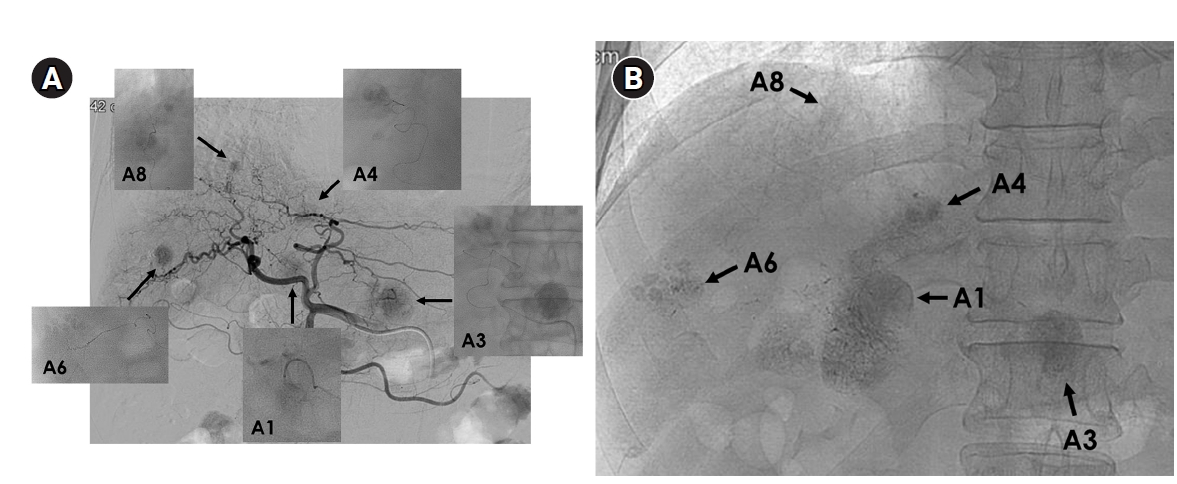

Fig. 4.

Superselective transarterial chemoembolization (TACE) for five nodular tumors in a 60-year-old man. (A) Common hepatic arteriography shows five nodular tumors. Superselective TACE was performed through tumor-feeding arteries including A1, A3, A4, A6, and A8. (B) Post-TACE fluoroscopy shows dense lipiodol uptake within the tumors without significant parenchymal deposition.

Fig. 6.

Sequential transarterial radioembolization (TARE) followed by transarterial chemoembolization (TACE) in a 77-year-old man with large hepatocellular carcinoma. (A) Magnetic resonance imaging and angiography show a 12.5-cm conglomerated mass (arrows) with multiple satellite nodules in segments 5, 6, and 7. (B) Sequential TARE was planned because a single session could not achieve sufficient tumor dose owing to lung dose limitation. In TARE #1 (5.0 GBq resin microspheres), perfused liver dose was 178 Gy and lung dose was 9.6 Gy. In TARE #2 (5.5 GBq resin microspheres), perfused liver dose was 255 Gy and lung dose was 12.2 Gy. Post-treatment Y-90 positron emission tomography/computed tomography demonstrates heterogeneous intratumoral Y-90 activity in the tumors. (C) Angiography 5 months after TARE #2 shows decreased tumor staining (arrows) in the right lobe. TACE was performed through multiple subsegmental branches supplying residual tumor. (D) After two additional TACE sessions (not shown), the computed tomography obtained 2 years after the initial TARE showed decreased tumor size, near-complete disappearance of arterial enhancement, and partial lipiodol uptake (arrows) in the tumor.

Fig. 4. Superselective transarterial chemoembolization (TACE) for five nodular tumors in a 60-year-old man. (A) Common hepatic arteriography shows five nodular tumors. Superselective TACE was performed through tumor-feeding arteries including A1, A3, A4, A6, and A8. (B) Post-TACE fluoroscopy shows dense lipiodol uptake within the tumors without significant parenchymal deposition.

Fig. 6. Sequential transarterial radioembolization (TARE) followed by transarterial chemoembolization (TACE) in a 77-year-old man with large hepatocellular carcinoma. (A) Magnetic resonance imaging and angiography show a 12.5-cm conglomerated mass (arrows) with multiple satellite nodules in segments 5, 6, and 7. (B) Sequential TARE was planned because a single session could not achieve sufficient tumor dose owing to lung dose limitation. In TARE #1 (5.0 GBq resin microspheres), perfused liver dose was 178 Gy and lung dose was 9.6 Gy. In TARE #2 (5.5 GBq resin microspheres), perfused liver dose was 255 Gy and lung dose was 12.2 Gy. Post-treatment Y-90 positron emission tomography/computed tomography demonstrates heterogeneous intratumoral Y-90 activity in the tumors. (C) Angiography 5 months after TARE #2 shows decreased tumor staining (arrows) in the right lobe. TACE was performed through multiple subsegmental branches supplying residual tumor. (D) After two additional TACE sessions (not shown), the computed tomography obtained 2 years after the initial TARE showed decreased tumor size, near-complete disappearance of arterial enhancement, and partial lipiodol uptake (arrows) in the tumor.